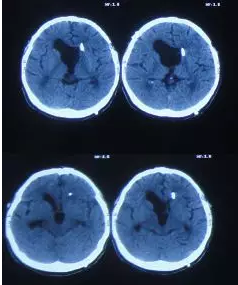

内镜造瘘术后第4天即脑室外引流拔除后第2天即2012年5月2日,腰穿提示颅内压高达400mmH20,查头CT:三脑室又扩大(图-4),查头MRI:小脑扁桃体轻微下疝(图-5),医生考虑三脑室再次扩大跟小脑扁桃体下疝有关,给予腰大池引流相关治疗。

图-4:2012年5月2日头CT

图-5:2012年5月2日头MRI

查头颅CT:脑室扩张,左侧侧脑室外引流术后状态(图-6)。

图-6:2012年5月4日头CT